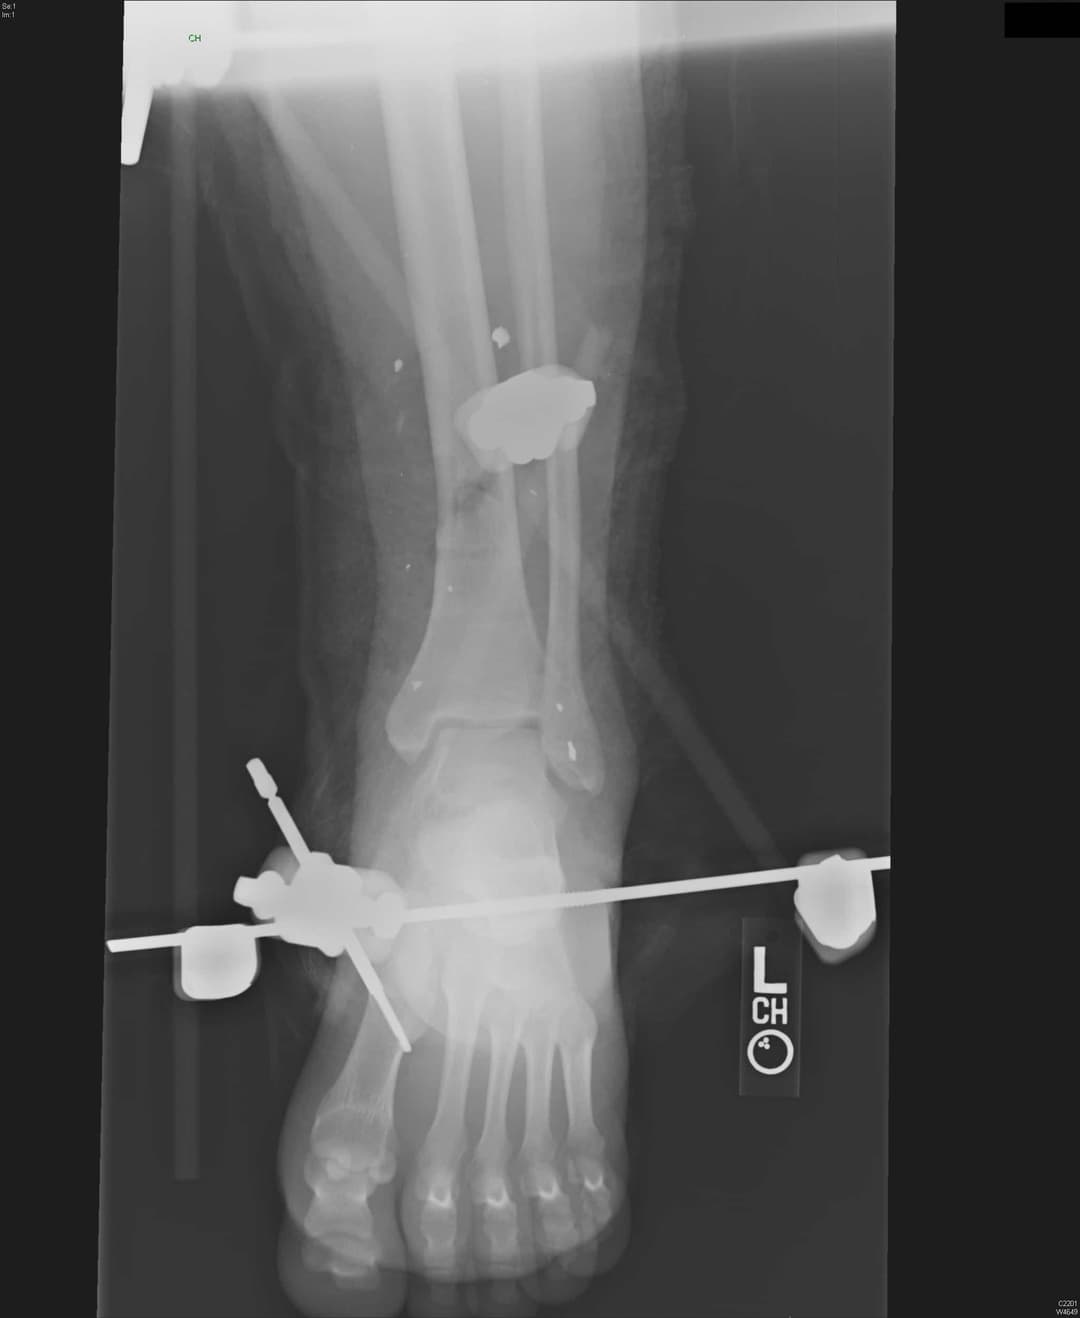

4. див. зобр. 10. Передньозадня рентгенограма зовнішнього фіксатора гомілковостопного суглоба зі штифтом для трансфіксації п’яткової кістки таштифтом першої плеснової кістки.

Зобр. 10